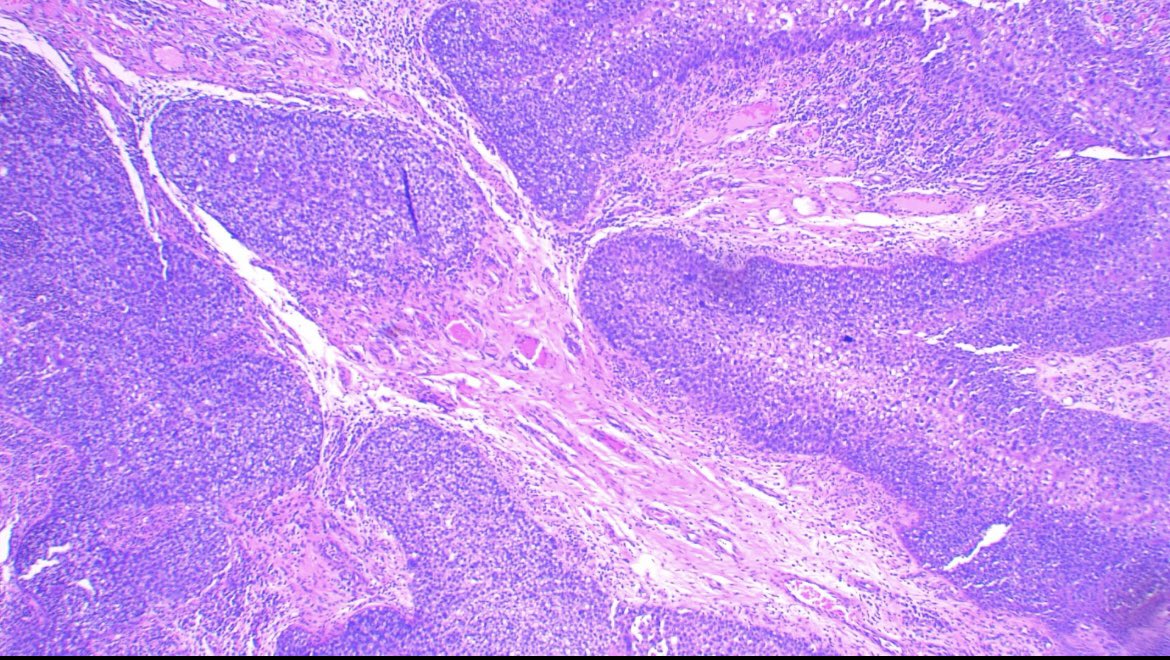

Make the Dx: ASDP October Case Study 85-year-old man with purpuric macules and papules at the abdomen, hips, and bilateral lower legs...… Learn more at asdpcasestudy.secure-platform.com/site/organizat… #asdpcasestudy; #dermatopathology; #dermpath